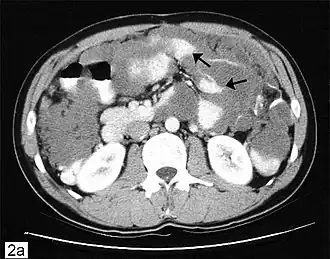

Компьютерная томограмма брюшной полости с изображением псевдомиксомы брюшной полости с рассеянными перитонеальными массами (стрелки). | |

Данное заболевание часто выявляется при хирургических операциях, проводимых по другим показаниям (удаление грыж), при этом опытный патолог может подтвердить диагноз. На последующих стадиях рассеянные опухоли пальпируются в абдоминальной области. Может выявляться вздутие живота, а также «желеподобный живот»[1] (сленговый медицинский термин, используемый для данного заболевания). В силу редкости заболевания, важна постановка точного диагноза для назначения соответствующего лечения. Диагностические процедуры могут включать проведение компьютерной томограммы, гистологического и иммуногистохимического исследования образцов, полученных при проведении диагностической лапароскопии. В качестве косвенных признаков может быть использовано проведение анализов крови на выявление онкомаркеров (РЭА, CA242). В большинстве случаев гастроскопия и колоноскопия оказываются неэффективными диагностическими средствами, поскольку рак аппендикса поражает брюшную полость, но не толстый кишечник (следует иметь в виду имеющиеся сообщения о редких случаях распространения рака аппендикса на кишечник). Ирригоскопия в ряде случаев указывает на дисфункцию илеоцекального клапана, расположенного в непосредственной близости от аппендикса. Позитронно-эмиссионная томография может быть использована для оценки злокачественной муцинозной аденокарциномы, однако данный тест не подходит для оценки доброкачественной разновидности опухоли, поскольку не может выявить теневое изображение новообразования. Магнитно-резонансная томография в настоящее время адаптируется для мониторинга заболевания, однако обычные магнитно-резонансные томографы как правило не используются в качестве диагностического инструментария. Диагноз также может быть подтвержден в патологических исследованиях.